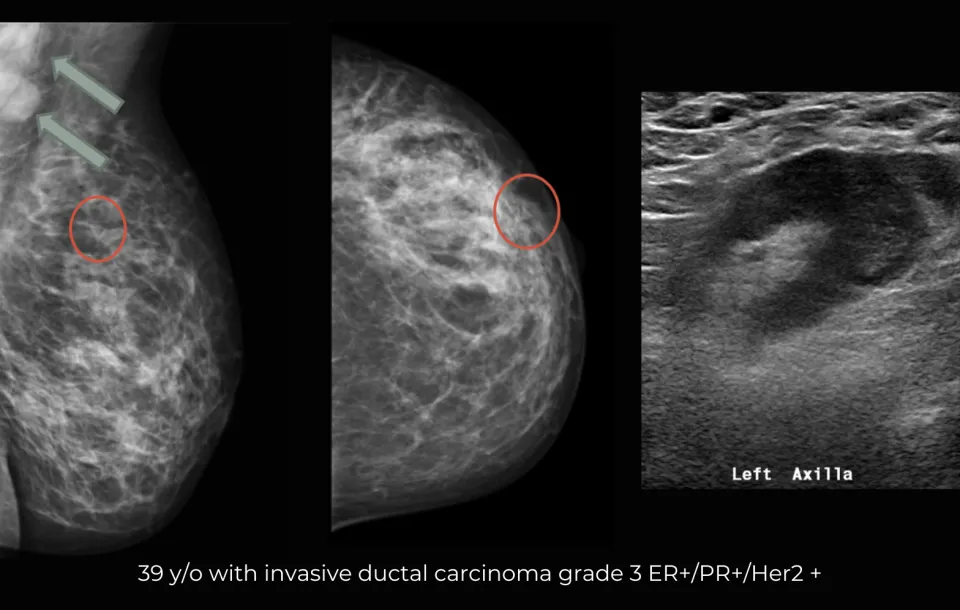

- Case studies with correlation with multiple modality imaging

- Case studies with multiple breast imaging modalities